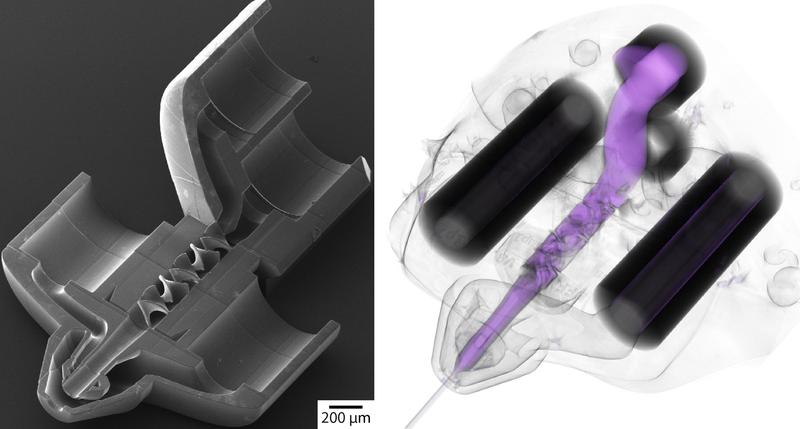

Forschende der Universität Stuttgart entwickeln nadelspitzengroßes Miniaturlabor

3D-Druck hat in den letzten Jahren die Herstellung von komplizierten Formen revolutioniert. Mithilfe von serieller Auftragung, bei der Punkt für Punkt oder…